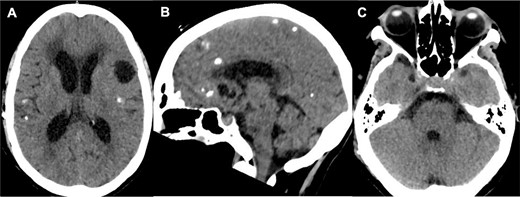

A 66-year-old woman presented with ataxia and dysmetria. She had a past medical history of hydrocephalus and seizures secondary to neurocysticercosis that merited medical management with a 30-day protocol of albendazole administration at 15 mg/kg/d and placement of a ventriculoperitoneal shunt (Fig. 1). Over the year before admission, brain imaging revealed multiple and increasing cystic lesions in the right cerebellar hemisphere (Fig. 2A–C). Besides, a follow-up brain MRI with contrast revealed multiple contrast-enhancing cysts compressing the fourth ventricle, perilesional edema, and an extra ventricular component next to the cerebellar tentorium (Fig. 2D–F).

Initial brain CT revealed multiple calcified cysts with ventriculomegaly in the axial (A, C) and sagittal (B) views.